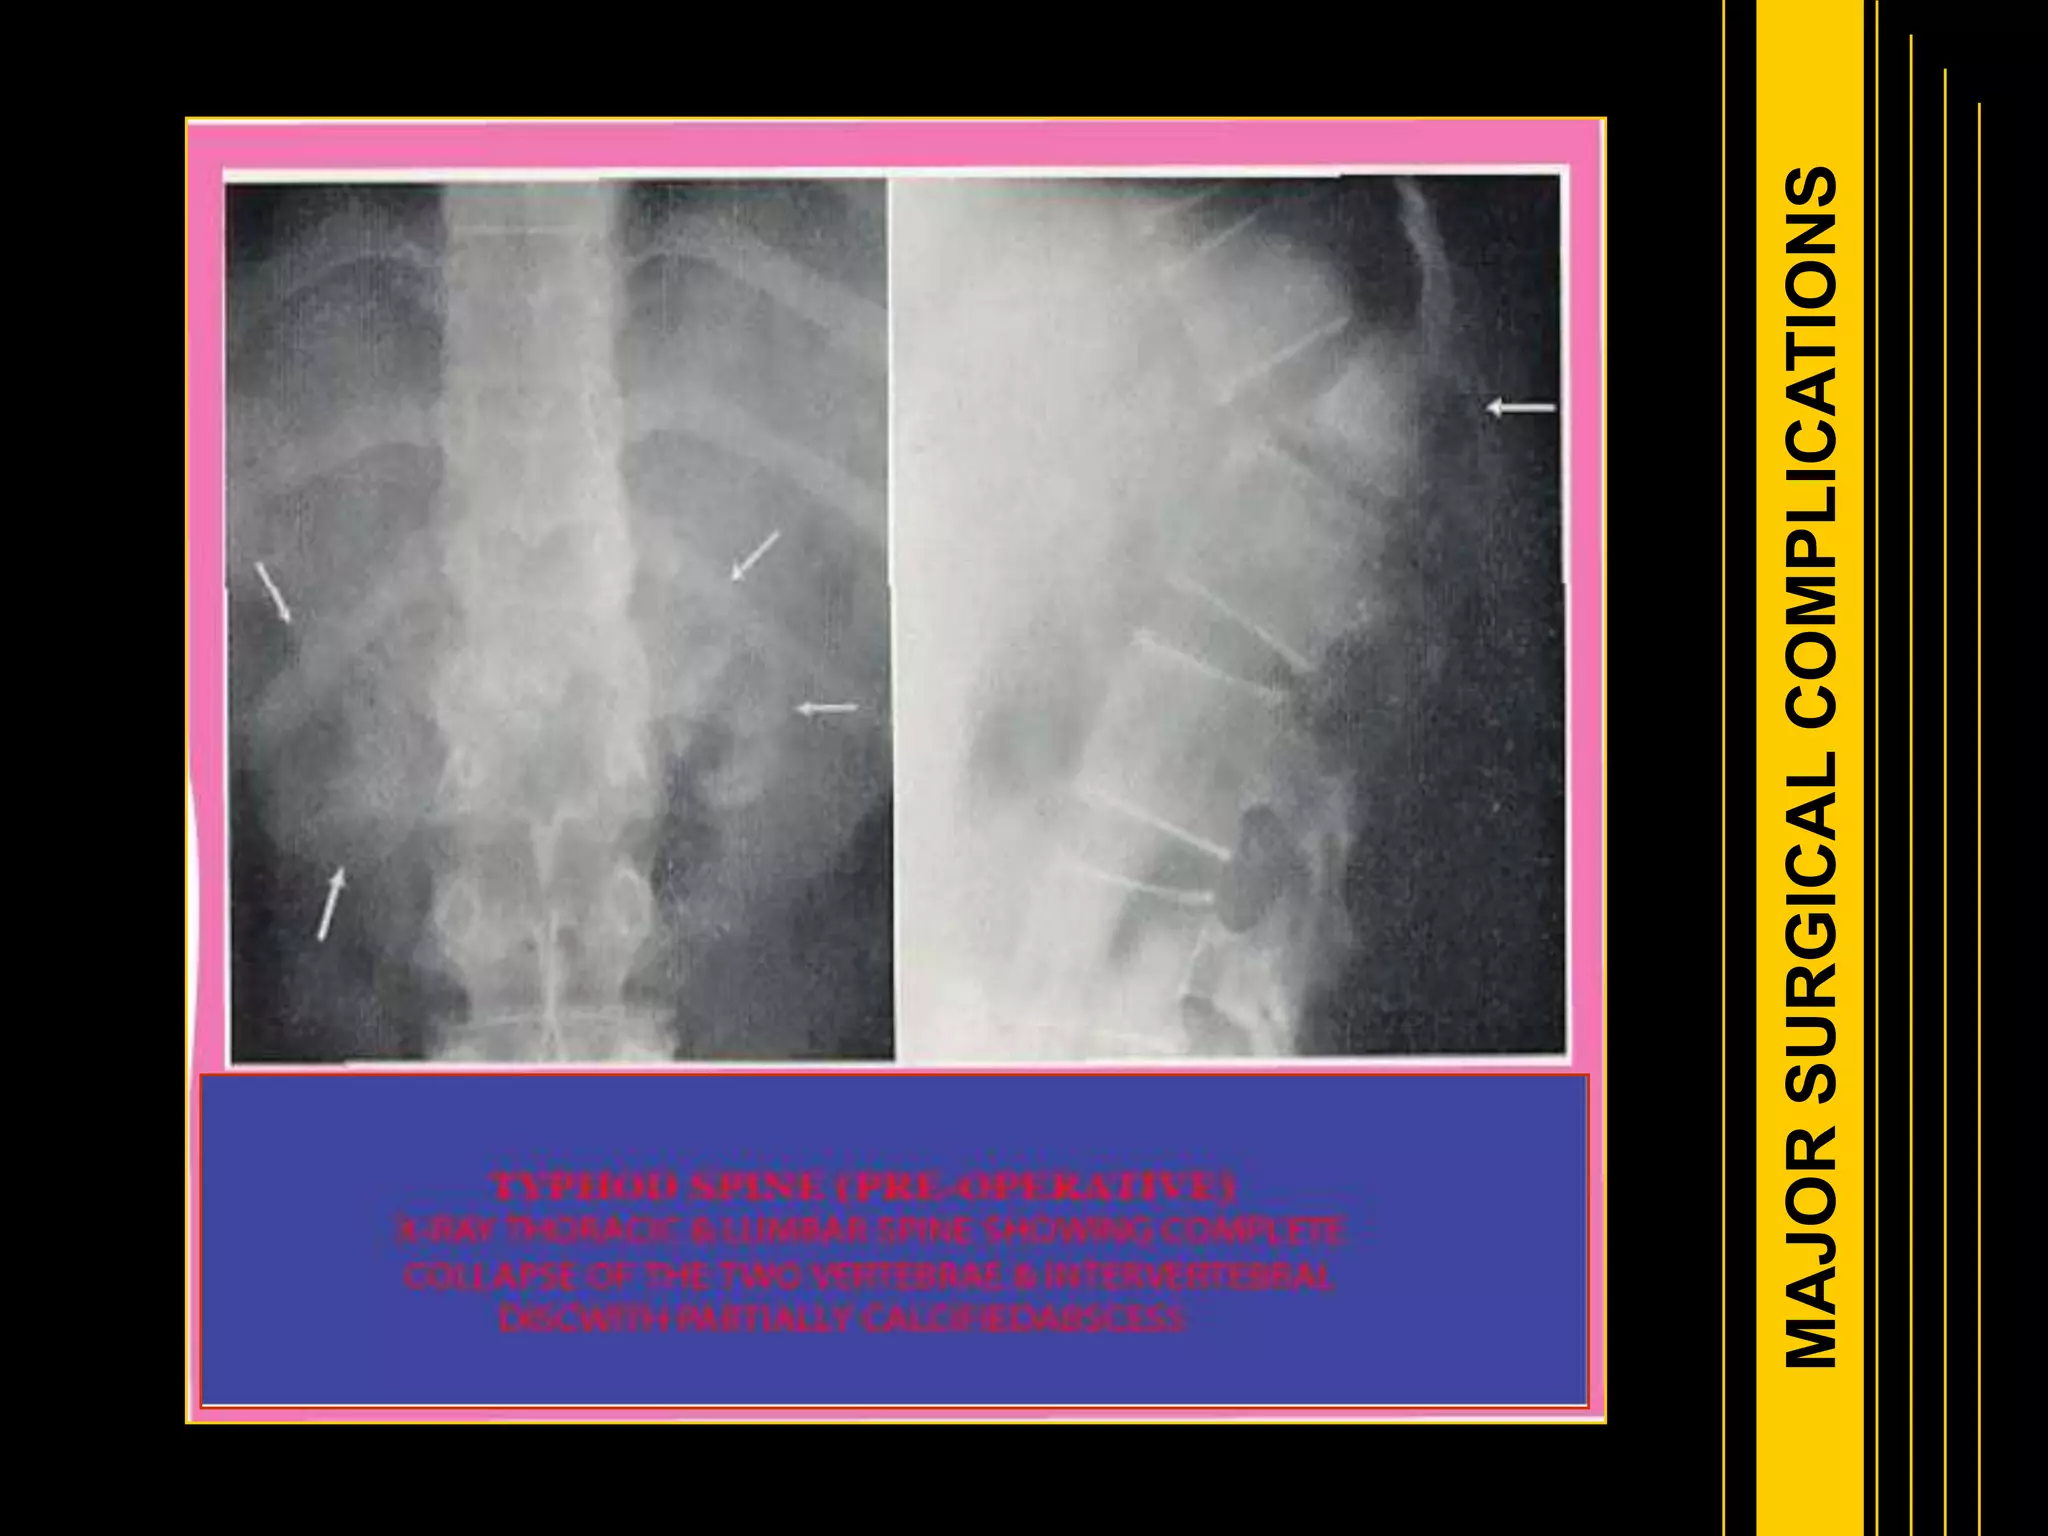

Typhoid fever is caused by the bacterium Salmonella typhi. It remains a major public health problem, infecting over 21 million people annually and causing over 200,000 deaths per year globally. The disease is transmitted through contaminated food or water. Clinical features include a sustained high fever over several weeks and complications can include intestinal bleeding or perforation. Diagnosis is made through blood or stool cultures. Treatment involves antibiotics. Prevention relies on vaccination, improved sanitation and hygiene practices like handwashing to control the spread from infected cases and carriers.